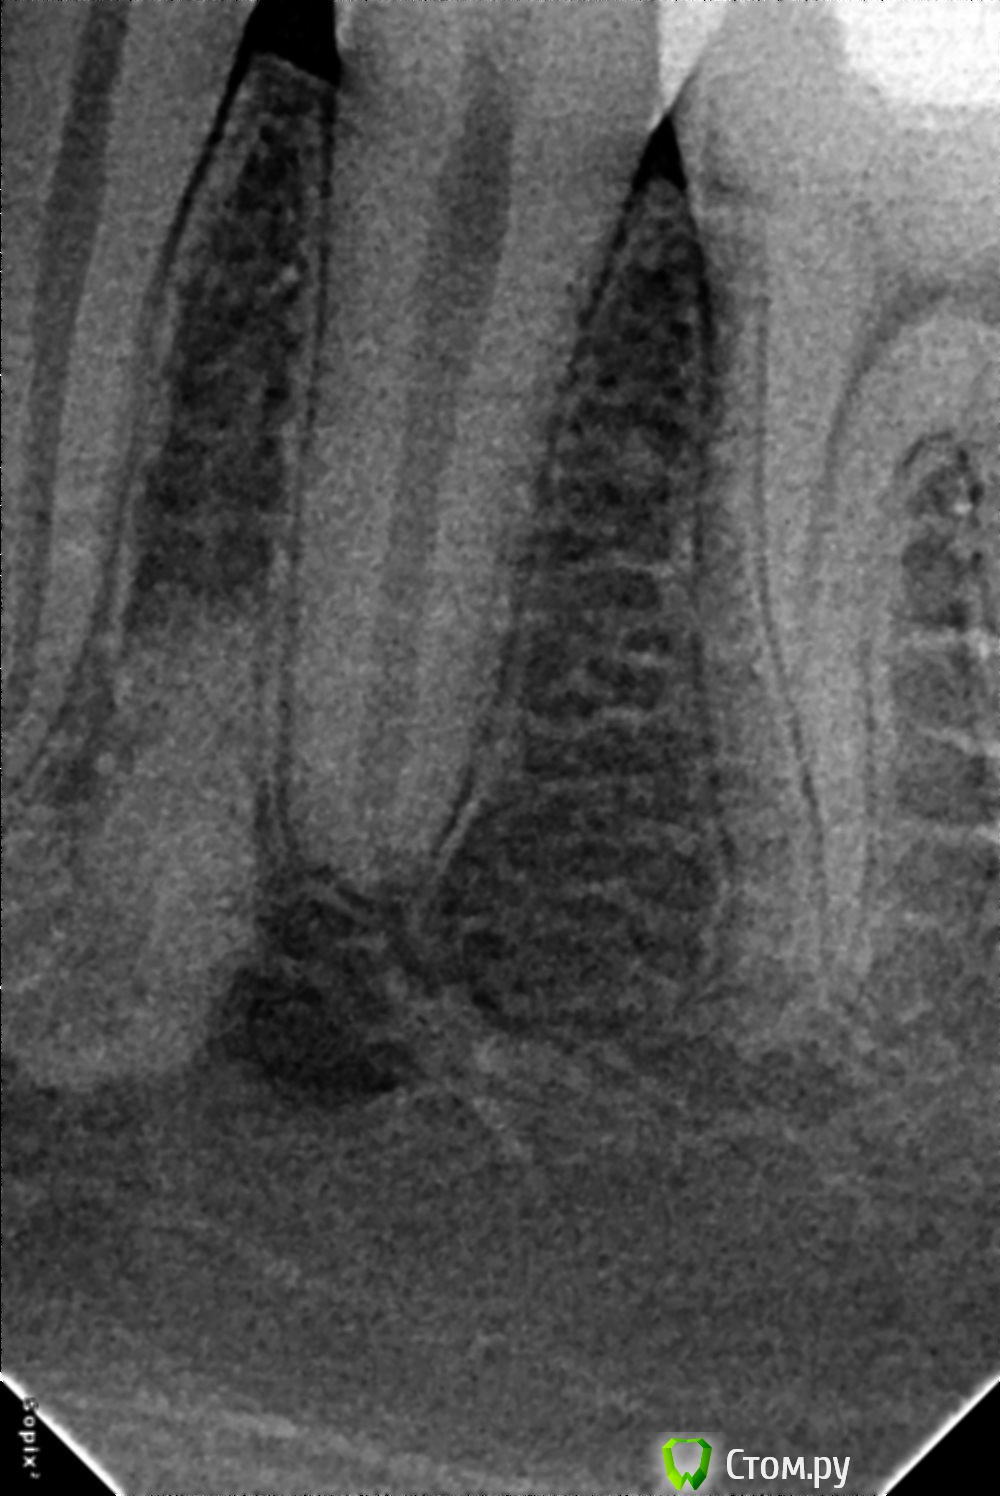

nurseit Опубликовано 13 января, 2014 Поделиться Опубликовано 13 января, 2014 Доброго времени суток, Уважаемые коллеги. 1 снимок сделан 30.03.2012. Второй 09.01.2014. Разница, почти 2 года. Интересует область 34,35 корней зубов. 1. Что это?2. Какова тактика? Ссылка на комментарий

nurseit Опубликовано 13 января, 2014 Автор Поделиться Опубликовано 13 января, 2014 Ещё прицельный снимок. Ссылка на комментарий

Afffinity Опубликовано 13 января, 2014 Поделиться Опубликовано 13 января, 2014 В области 34 гиперцементоз, а в области 35 похоже на foramen mentale. 1 Ссылка на комментарий

zzkz Опубликовано 14 января, 2014 Поделиться Опубликовано 14 января, 2014 Доброго времени суток, Уважаемые коллеги. 1 снимок сделан 30.03.2012.Второй 09.01.2014. Разница, почти 2 года. Интересует область 34,35 корней зубов. 1. Что это?2. Какова тактика?в динамике вроде норм. ничего не делать/наблюдать Ссылка на комментарий